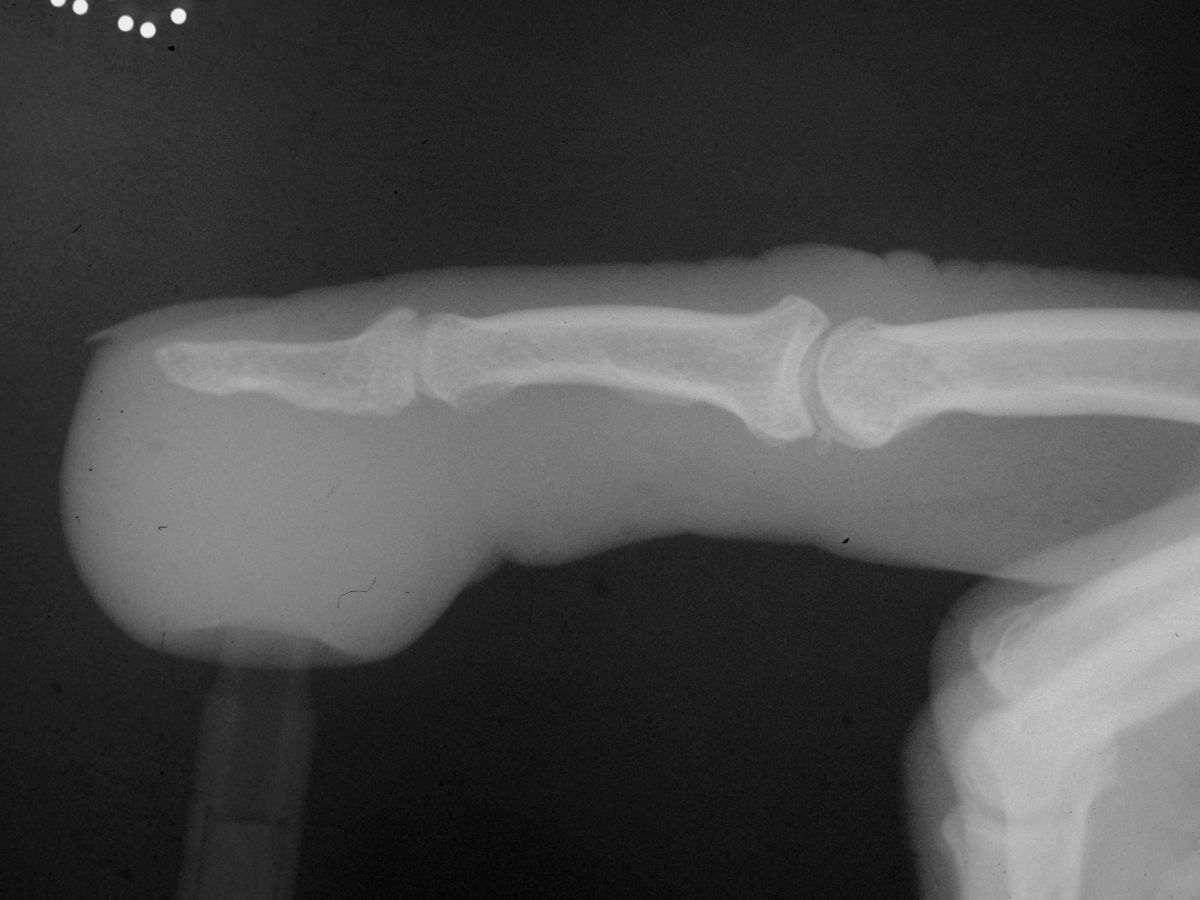

Plain Radiographs demonstrate soft tissue swelling only.